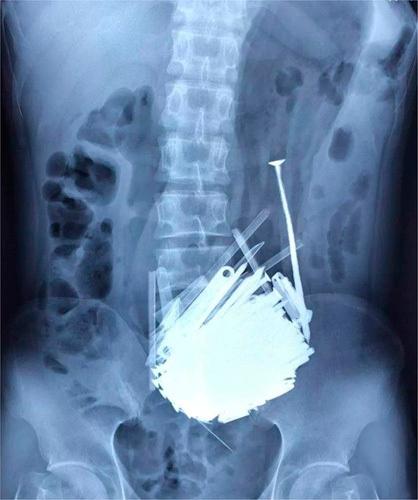

The authors present the case of a 39-year-old man who arrived at the hospital with symptoms of abdominal distension and occasional black stools for a week. The patient was known to have schizophrenia but had not received regular hospital follow-up or treatment for the past 5 years. He had a history of exogenous stimulation, which led him to surreptitiously swallow metallic objects. Upon physical examination, he displayed abdominal distension and mild tenderness in the upper abdomen. Radiographs revealed multiple foreign objects in his stomach, leading to the decision for laparotomy, gastric opening, and removal of the foreign objects under general anesthesia.

作者介绍了一名39岁男性的病例,该患者因腹胀和偶尔黑便症状入院,症状持续一周。已知该患者患有精神分裂症,但在过去5年中未接受正规的医院随访或治疗。他有过外部刺激史,这导致他偷偷吞食金属物品。体格检查时,他表现出腹胀和上腹部轻度压痛。X光片显示他胃内有多个异物,因此决定在全身麻醉下进行剖腹手术、打开胃部并取出异物。